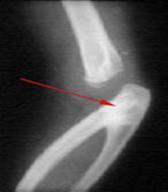

Рис.4. Рентгенограмма ребенка с радиоульнарным синостозом.

У ребенка рука не поворачивается в запястье (невозможна супинация и пронация), но сгибание и разгибание в локтевом суставе сохранены. Такое положение значительно усложняет жизнь больного, даже его самообслуживание. Лечение сначала консервативное и заключается в разработке. Некоторые больные могут хорошо приспосабливаться к этому дефекту. Если разработать руку не удается, выполняется оперативное лечение. При небольшом сращении выполняют его рассечение, при размере сращения больше 4 см прибегают к удалению части лучевой кости. Оперативное лечение выполняют в возрасте 3 лет.